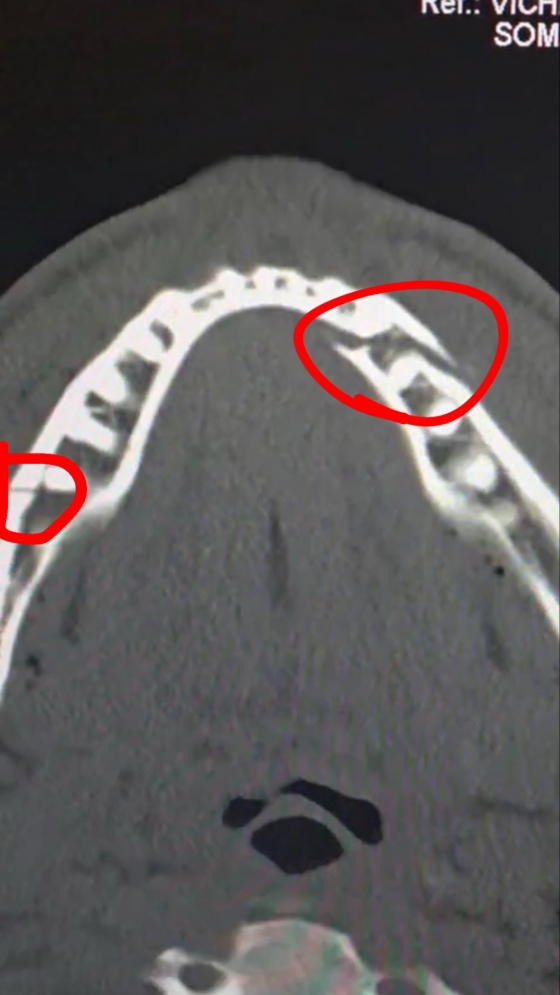

하지만 6라운드 1분 31초경 조슈아의 강력한 오른손 스트레이트가 폴의 턱에 정통으로 꽂혔고, 폴의 턱뼈는 두 곳이나 박살 나며 경기는 그대로 종료됐다.

경기 후 정밀 검사 결과 폴의 상태는 예상보다 훨씬 심각했다. 폴은 곧바로 병원으로 후송되어 턱뼈를 고정하기 위해 4개의 티타늄 플레이트를 삽입하고 일부 치아까지 제거하는 대수술을 받았다.

폴은 스포츠 전문 채널 'DAZN'과 인터뷰에서 "턱에 네 개의 판을 박았다. 회복 과정이 너무 힘들다"라며 고충을 토로했다.